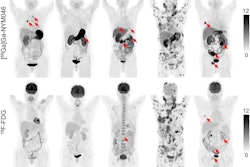

An autoradiography image showing the simultaneous biodistribution of Lutetium-177 and Actinium-225 radionuclides in colon cancer xenografts in mice.Image courtesy of Sara Rinne, PhD

According to the findings, the autoradiography showed general overlap between Lu-177 and Ac-225 in the tumors 24 hours after co-injection, with the combination therapy as equally potent as monotherapy for inducing tumor shrinkage.

In this study, the group performed serial biodistribution experiments in mice with subcutaneous GPA33-positive xenografts to determine if co-injection would alter their uptake and distribution, and to determine the injected activity needed to destroy the tumors.

They then imaged tissue samples using an ionizing-radiation quantum imaging detector (iQID), a scintillation camera that can visualize the distribution of small amounts of radiotracers within thin tissue sections.